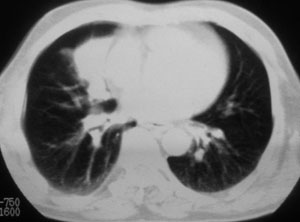

性别 男  62岁 因咳嗽及左肱骨剧烈痛疼数天来院检查。

右中央型肺癌并肱骨转移。

考虑右肺中叶肺癌并左肱骨转移伴病理性骨折。

支持右肺中心型肺癌并肺内及左肱骨转移伴病理性骨折

右肺中心型肺癌并中叶不张,左肱骨溶骨性转移并病理骨折。